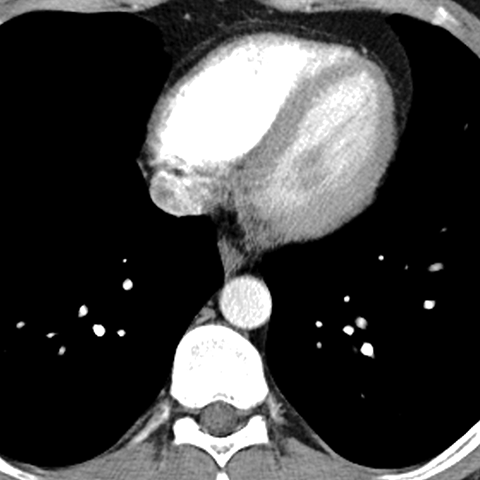

Normal Mediastinum (Axial CT) [5 of 5]